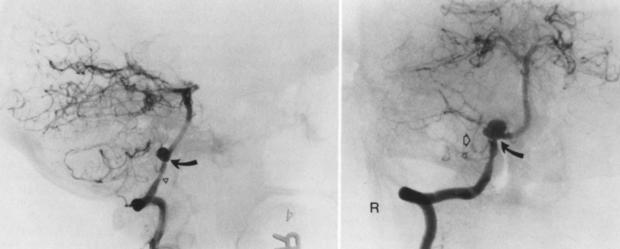

وقال استشاري ومدرس جراحة المخ والأعصاب إنه من الطبيعي أن يضل الدم للمخ عن طريق شرايين كبيرة ثم شرايين صغيرة ثم شعيرات دموية، ولكن في حالة حدوث ضيق في الشرايين الكبيرة، والشعيرات الدموية، يحدث قصور في الدورة الدموية للمخ، وهنا تحدث المشكلات الصحية.

وأشار الدكتور أحمد كامل، إلى أنه يمكن العلاج باستخدام أدوية سيولة للوقاية من الجلطات، وتقليل الكوليسترول، مع السوائل وممارسة الرياضة، ولكن في حالة تفاقم الأمر تصل إلى العمليات الجراحية.

وأضاف أنه في حالة ضيق الشرايين وعدم وصول الدم للمخ يلجأ المريض للجراحة، ويتم عمل قسطرة ودعامة كدعامات القلب بشكل دقيق للغاية.

القسطرة والدعامة:

من خلال تركيب وحقنها بمادة للعلاج.